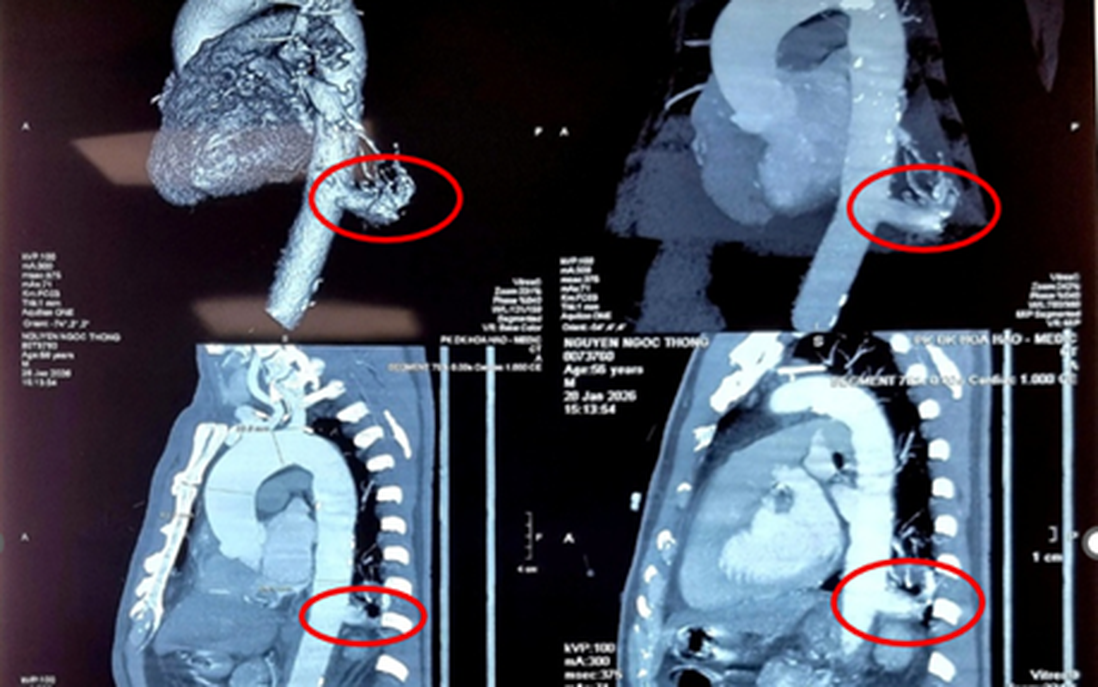

Theo đó, ông N.N.T (56 tuổi, quê Tây Ninh) tình cờ phát hiện bị tổn thương thùy dưới phổi trái khi đi khám tổng quát. Tại bệnh viện, các bác sĩ chẩn đoán ông mắc phổi biệt lập nội thùy với khối kích thước 23mm×26mm. Đáng chú ý, động mạch nuôi khối này xuất phát trực tiếp từ động mạch chủ xuống với đường kính lên tới 17mm - một kích thước rất lớn và đầy rủi ro nếu người bệnh không được điều trị.

ThS.BSCKII. Nguyễn Văn Việt Thành, Trưởng khoa Ngoại Lồng ngực - Bướu cổ, Bệnh viện Bình Dân, người trực tiếp thực hiện ca mổ cho biết: "Khó khăn lớn nhất là phẫu tích nhánh động mạch nuôi này. Mạch máu này to, dễ vỡ và rất dính do tình trạng nhiễm trùng mạn tính xung quanh. Một sai sót nhỏ cũng có thể dẫn đến biến cố chảy máu không thể kiểm soát". Trước thách thức đó, hội chẩn toàn viện đã quyết định lựa chọn phẫu thuật robot.